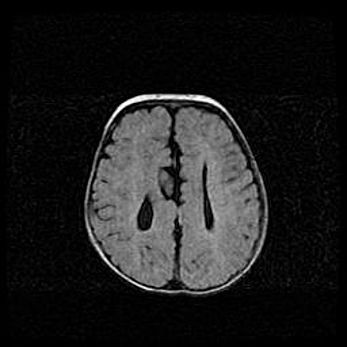

Лейкомаляция с кистозно-глиозной дегенерацией головного мозга.

Возраст: 2 месяца 25 дней

Вес: 6400 г

Окружность головы: 40 см

Срок гестации: 41 неделя

Лейкомаляцию относят к ишемически-гипоксическим повреждениям головного мозга, диагностируемым у новорожденных. При лейкомаляции в головном мозге обнаруживают очаги некроза, возникшие после тяжелой гипоксии и нарушения кровотока. В процессе морфогенеза очаги проходят три стадии: 1) развития некроза, 2) резорбции и 3) формирования глиозного рубца или кисты. Перивентрикулярная лейкомаляция (ПЛ) встречается примерно в 12% случаев среди новорожденных, обычно – у недоношенных детей, причем, частота ее зависит от массы, с которой младенец появился на свет. Наибольшее число малышей страдает лейкомаляцией, если масса при рождении 1500-2500 г.